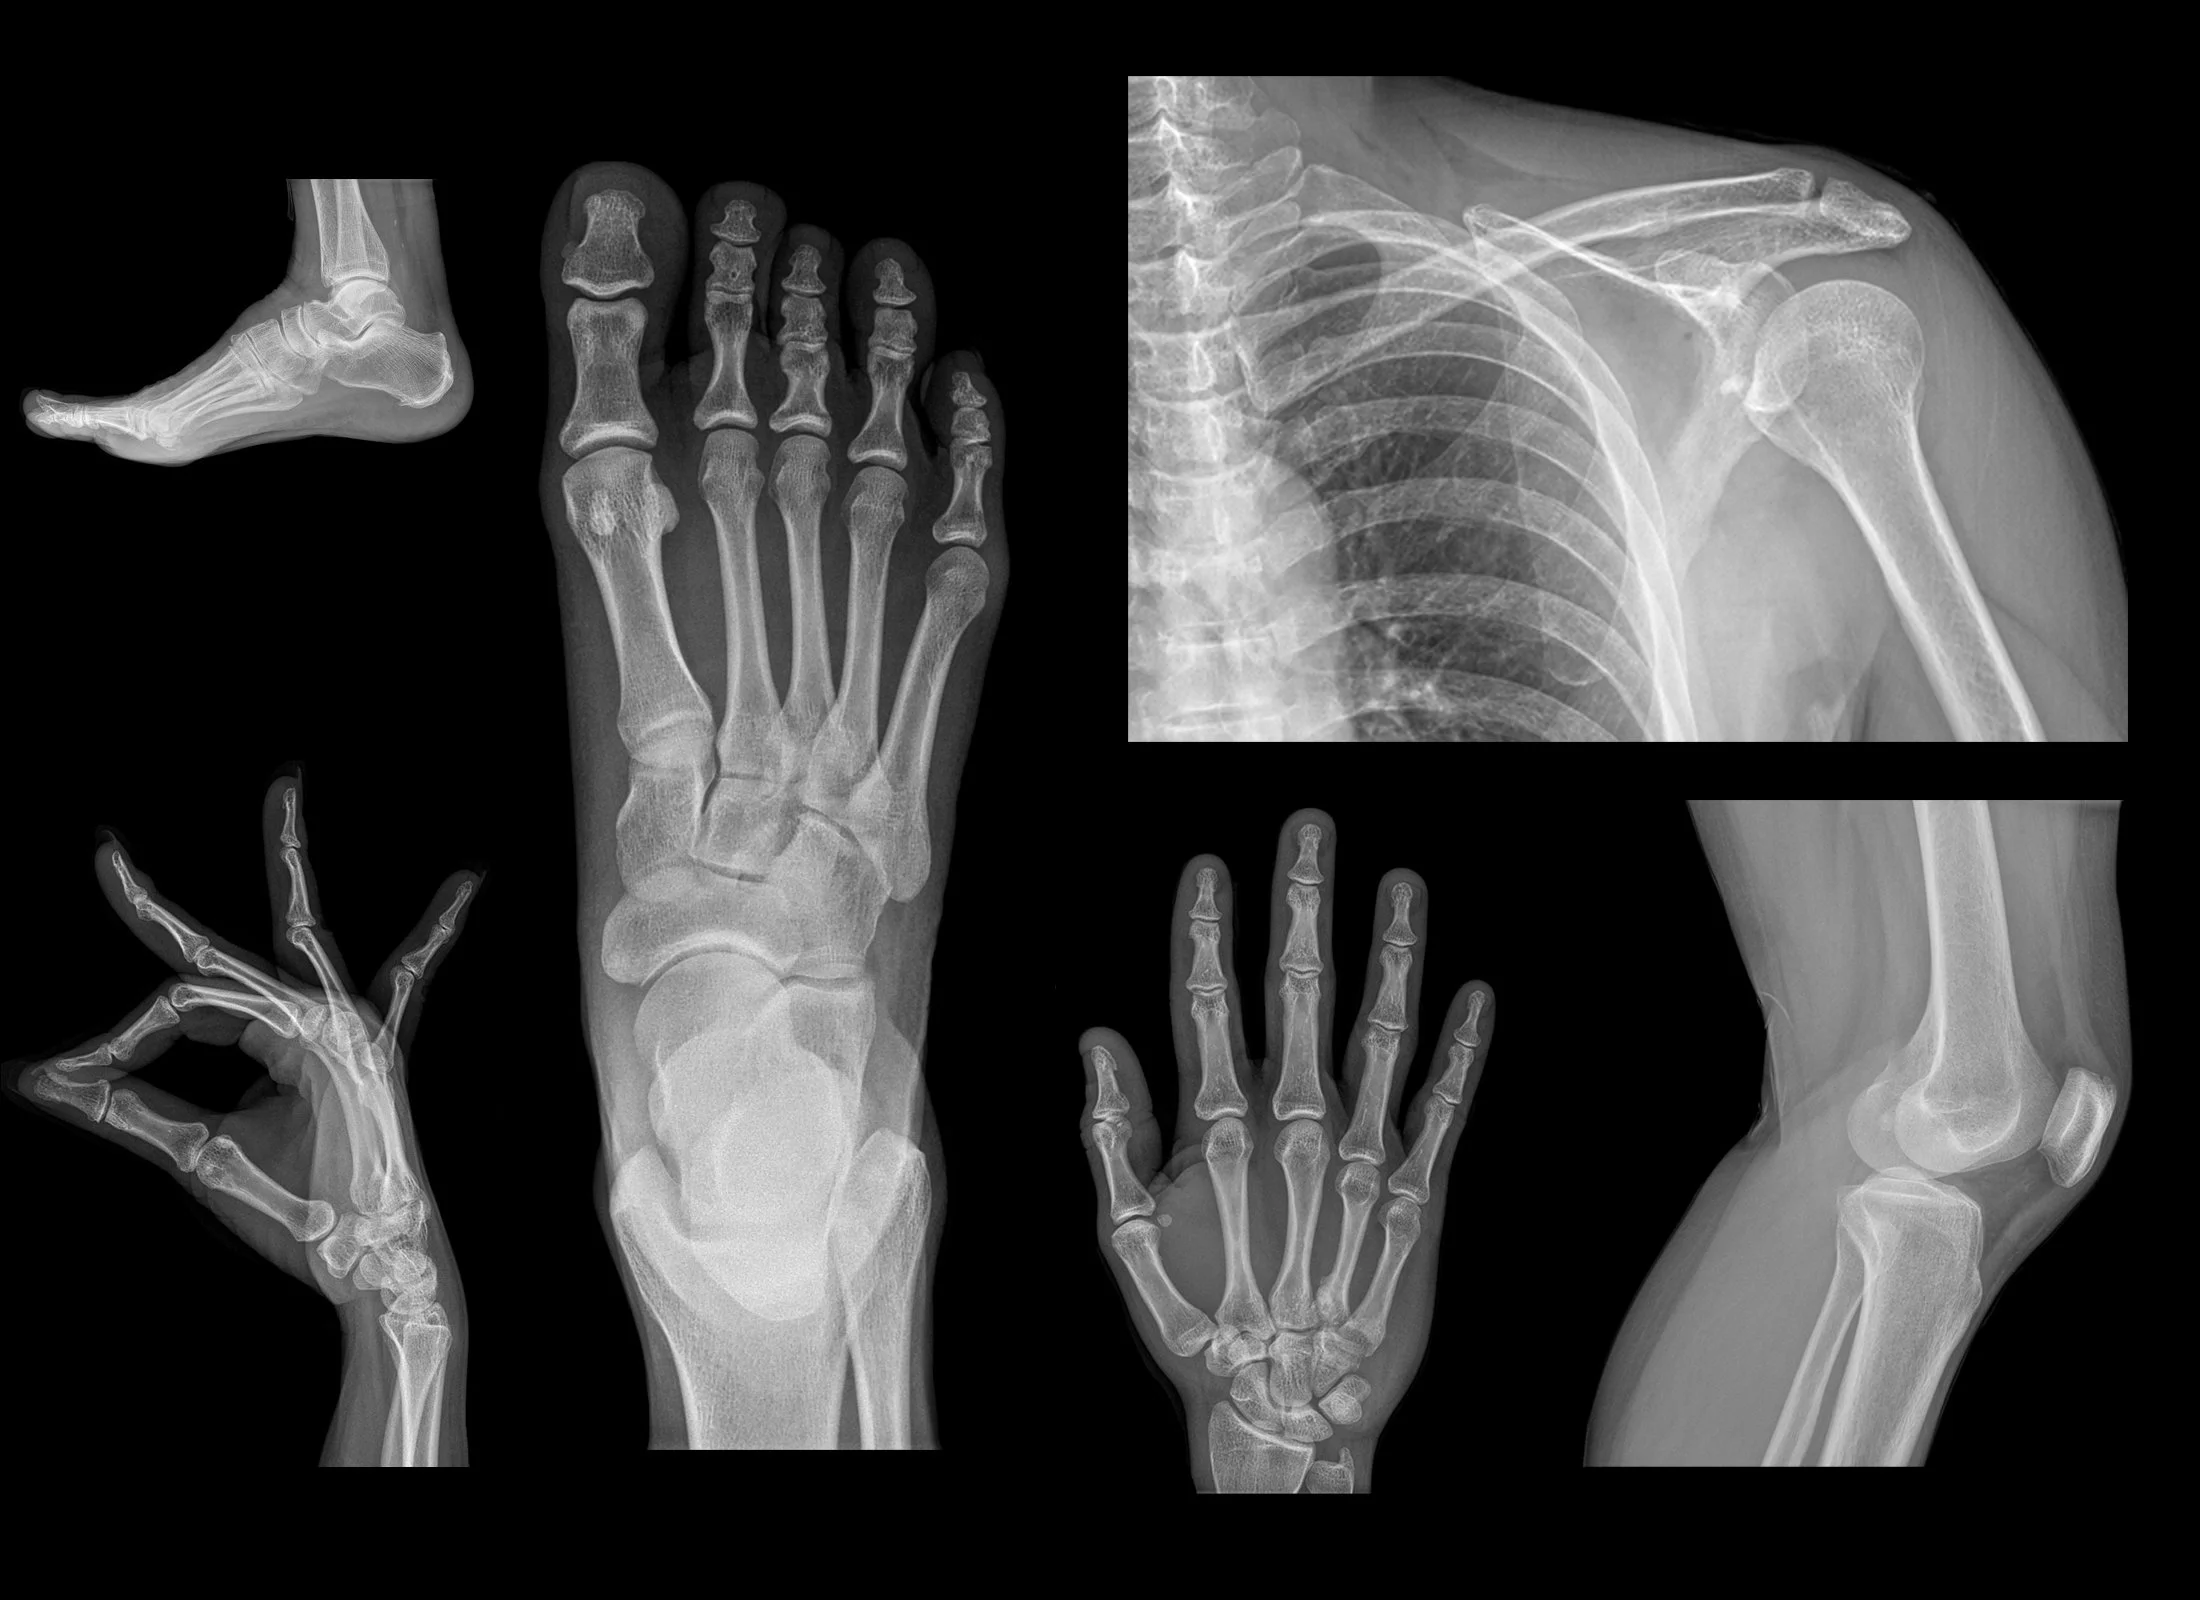

Our X-ray services offer quick and efficient imaging, making it an invaluable tool for diagnosing a wide range of medical conditions. Whether it's detecting fractures, assessing joint health, or evaluating the chest for respiratory concerns, X-rays provide rapid insights for timely medical decisions.

X-rays are highly versatile and can be used to examine various areas of the body, including bones, joints, and soft tissues. From identifying orthopedic issues to detecting abnormalities in the chest or abdomen, our X-ray services cover a broad spectrum of diagnostic needs.